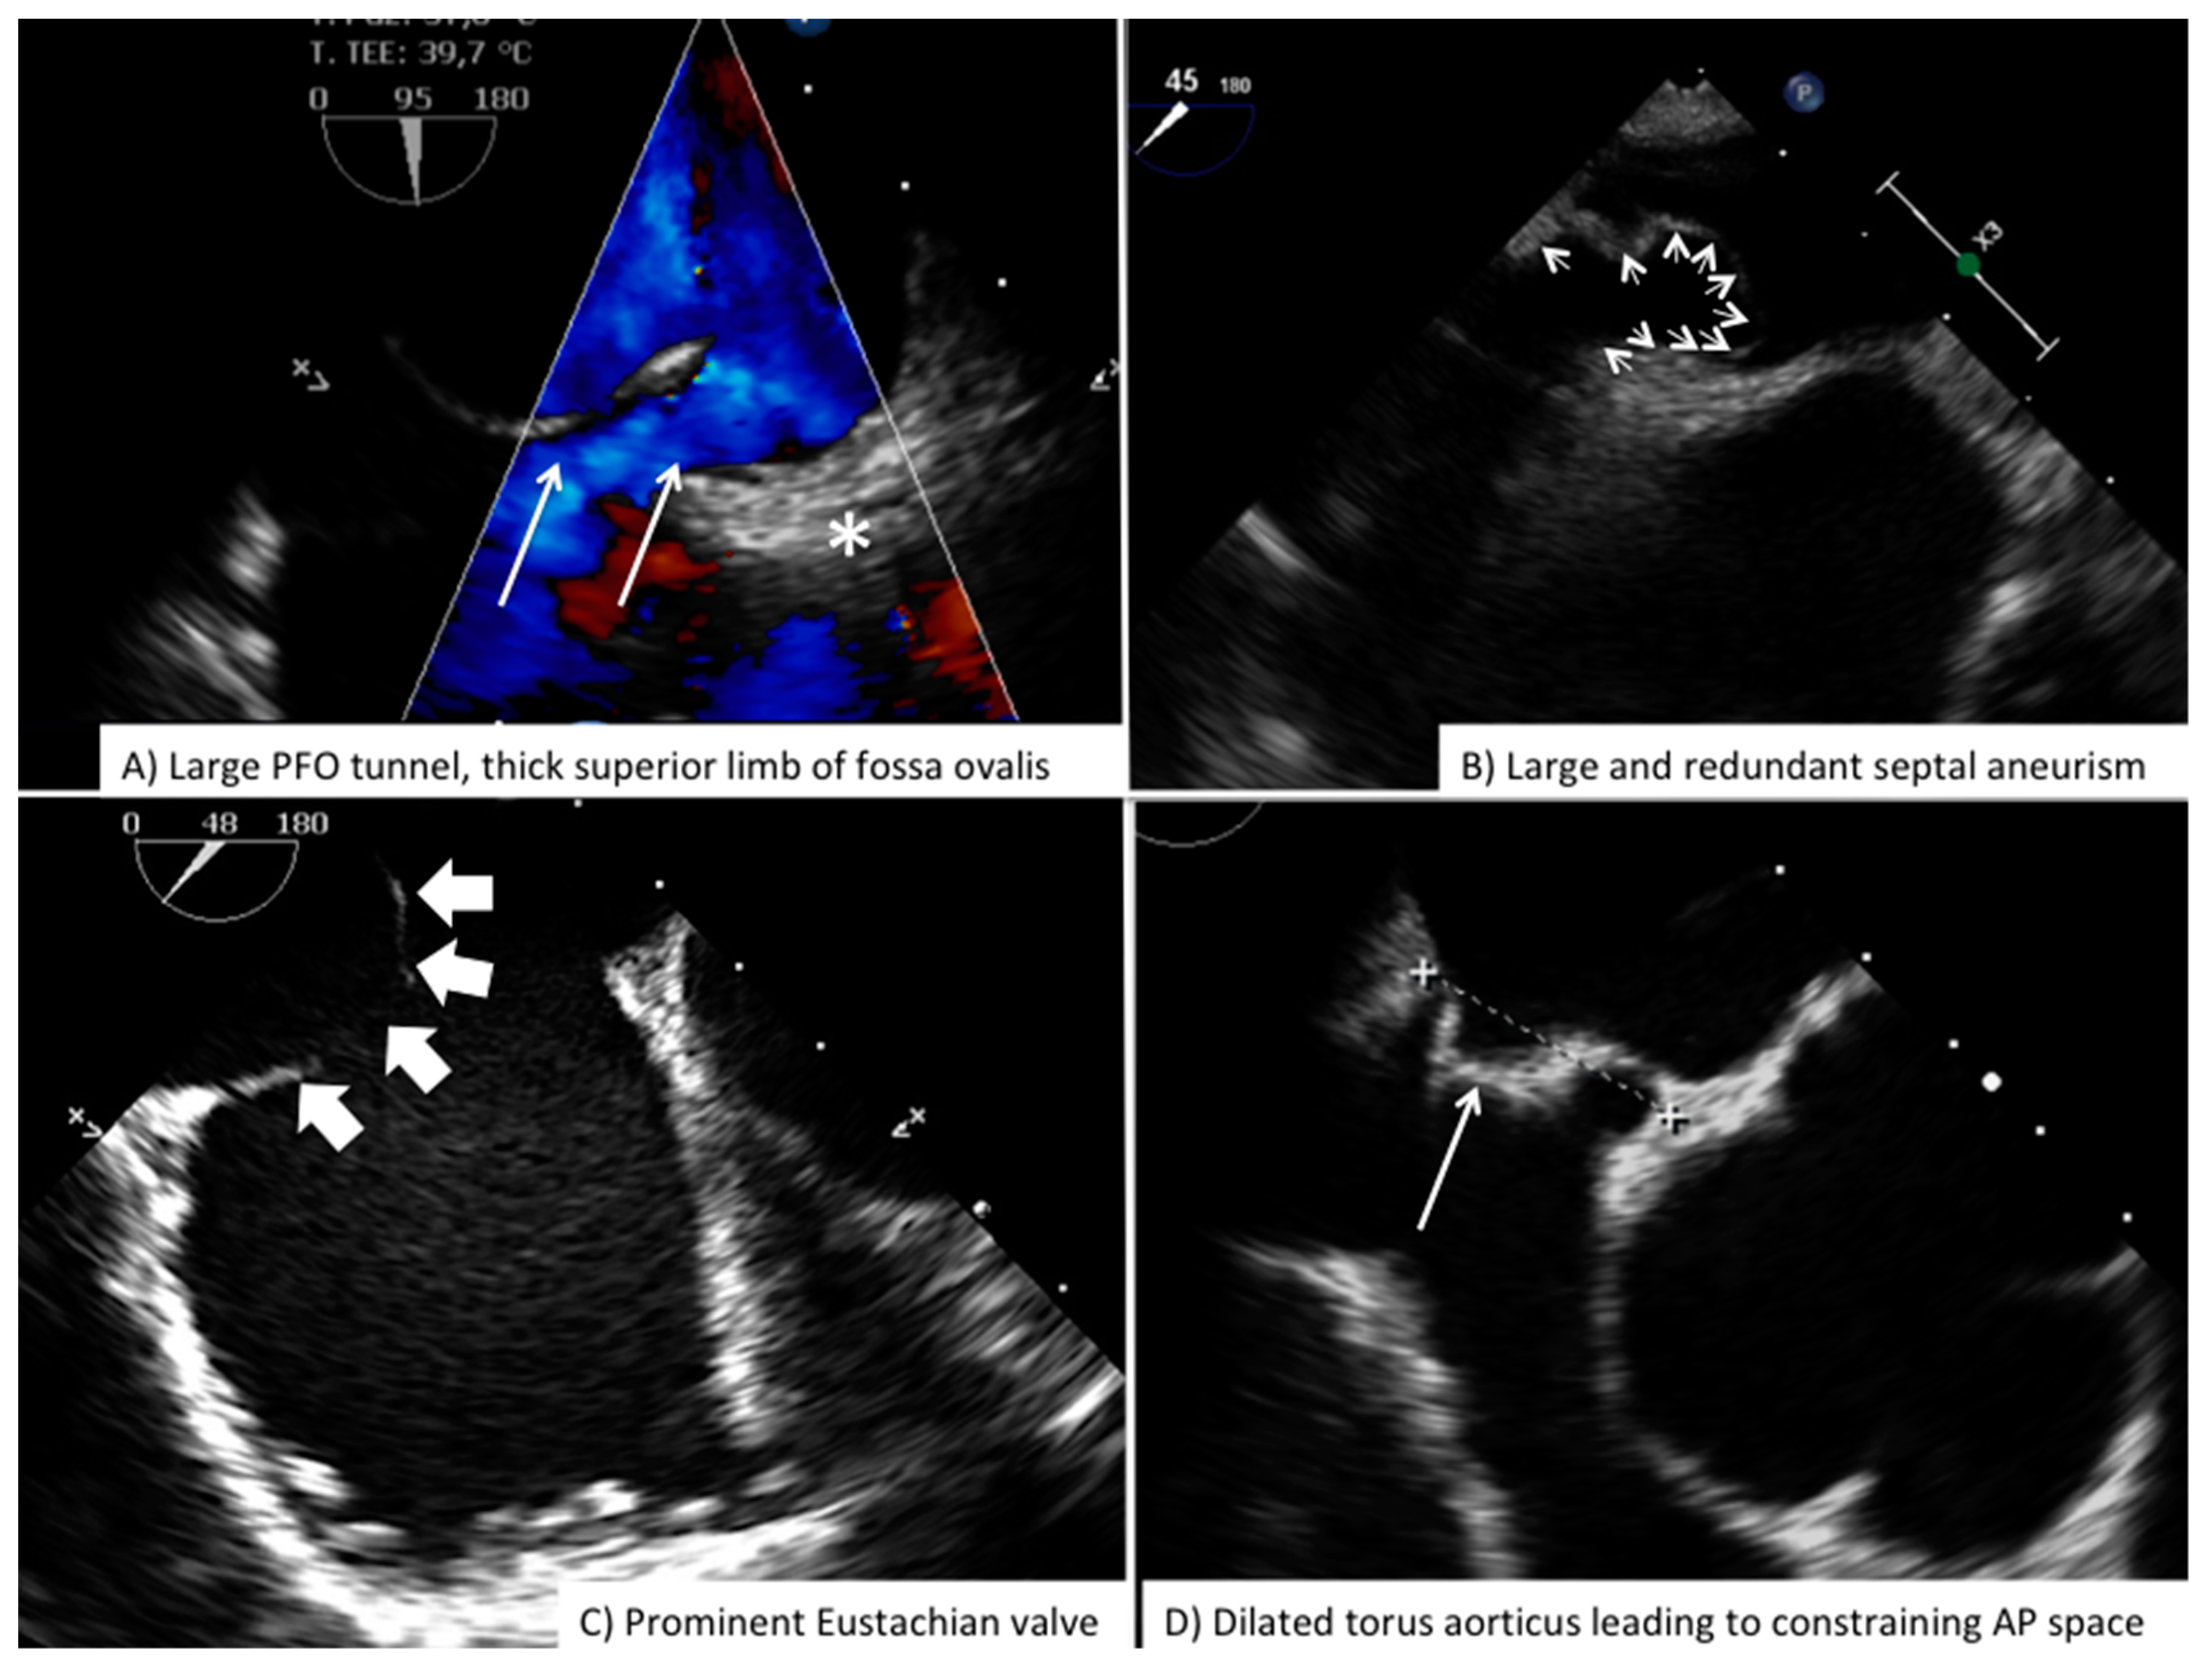

Procedural monitoring is usually carried using three main TEE views: (1) mid-esophageal long axis (90° bicaval view) of the atrial septum; (2) mid-esophageal short axis (45°–60° aortic view) of the atrial septum; (3) mid-esophageal 0° that is particularly useful to scan the posterior border of atrial septum (Table 2). Imager must confirm proper engagement of PFO tunnel by the wire. This is a key detail because, in the presence of accessory fenestration, wrong wire positioning within the fenestration will leave the PFO tunnel not engaged by the device and this will increase risk of device embolization and large residual shunt after deployment (Figure S3 Online Supplementary Material). Correct wire positioning across PFO tunnel is usually associated with enhanced separation between septum primum and superior limb of the fossa ovalis. The importance of a skilled echocardiographer, accustomed to every single step of the procedure as well as to the device currently in use, cannot be overemphasized. Knowing the differences in the echocardiographic appearance of the several available devices helps to readily recognize potential problems and to anticipate impending complications (Figure S4 Online Supplementary Material). Periprocedural imaging provides important information for the interventionalist regarding proper device to be used in that particular patient: (1) thickness of superior limb of the fossa ovalis (septum secundum); (2) length and amplitude of PFO tunnel during wire sizing; (3) hypermobility of septum primum or presence of septal aneurysm; (4) degree of shunt; (5) distance between the torus aorticus and posterior wall of atria (Figure 6). Fluoroscopic monitoring is essential, PFO crossing and subsequent device delivering is usually accomplished using left oblique anterior view with some cranial angulation. During deployment the imager needs to maintain the tip of the guiding sheath at the center of the image so to allow the interventionalist to avoid any direct contact between device and atrial wall. After deployment of left atrial disc, direct echocardiographic guidance will allow the interventionalist to retract the device-guiding sheath as a unit so to allow for complete contact of left atrial disk with atrial septum, often proper clockwise or counterclockwise rotation of the device-guiding sheath unit may be necessary to optimize proper alignment. After release of the right atrial disk, complete reassessment of device grasp onto the septum is of paramount importance and will need both bidimensional and color-Doppler scan both in long and short axis views with cranio-caudal swipe. Particular attention should be placed to exclude potential catching of Chiari network or large Eustachian valve within the device, good grasp on the superior and posterior border of atrial septum, complete coverage of the entire tunnel length, relatively well formed and parallel disks and absence of interference with surrounding cardiac structure (superior and inferior vena cava, coronary sinus, atrio-ventricular valves).

Figure 6. Challenging anatomies for PFO closure. Common anatomical features increasing procedural complexity and complication during PFO closure. PFO = Patent Foramen Ovale.